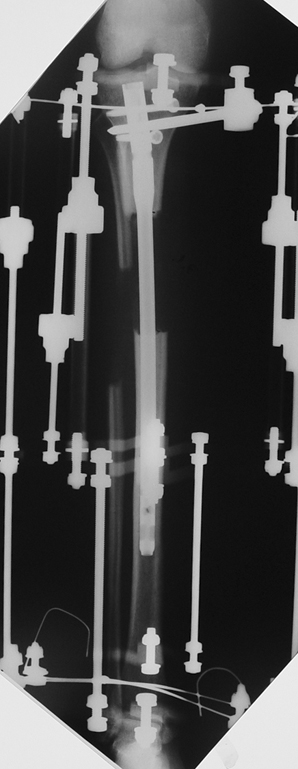

2. Step:

The application of the external fixator: Three Schanz screws are placed distally and three screws are placed proximally. At least 1 mm of distance shall remain between the screws and the nail.

Postoperative care: Distraction is commenced at day 10. 0,25 mm of lengthening is perfomed 4 times daily (every 6 hours). Hip and knee joint motion exercises begin at 1-2. day postoperatively. For many years, the treatment of lower extremity shortness has been very hard for the patient and the surgeon. The techniques developed after the introduction of Ilizarov’s distraction osteogenesis concept have pioneered a new era, and have been considered to be procedures in which previous complications are encountered much less frequently.

In selected cases, we prefer to use a combination of a unilateral dynamic axial fixator and an interlocked intramedullary nail, in order to protect the length and alignment after the completion of the lengthening procedure. As a prerequisite for this technique, the narowest diameter of the medullary cavity shall be wider than 7 mm and the length of the nail segment distal to the osteotomy site shall be at least 8 cm. after the completion of the lengthening procedure.The intramedullary nail neutralizes shear and bending forces on femur during lengthening, shortens external fixation time, and protects newly formed bone against fractures. In our series, subtrochanteric osteotomy was performed in one case. No varus angulation occured despite the intramedullary nail.

Ilizarov stressed the significance of endosteal blood circulation for distraction osteogenesis. Although we placed the intramedullary nail after reaming the femur in all cases, the time for callus formation was not longer than expected. Thus we found that there is no slowing in the rate of new bone formation due to disruption of medullary blood flow. The rationale of this finding is revascularization that occurs following reaming of the medullary cavity, the fixation stability with the intramedullary nail and early functional weight bearing. The potential disadvantages of a combined use of external and internal fixation metods are increased blood loss, intramedullary infection, risk of fat embolism and excessive metal load.The most fearsome complication is a deep intramedullary infection (panosteomyelitis) triggered by pin tract infection.No such complication was encountered in our series. In order to avoid this complication, after the completion of lengthening the nail shaill be interlocked from the medial side, and contact of internal and external fixator pins shall be avoided.